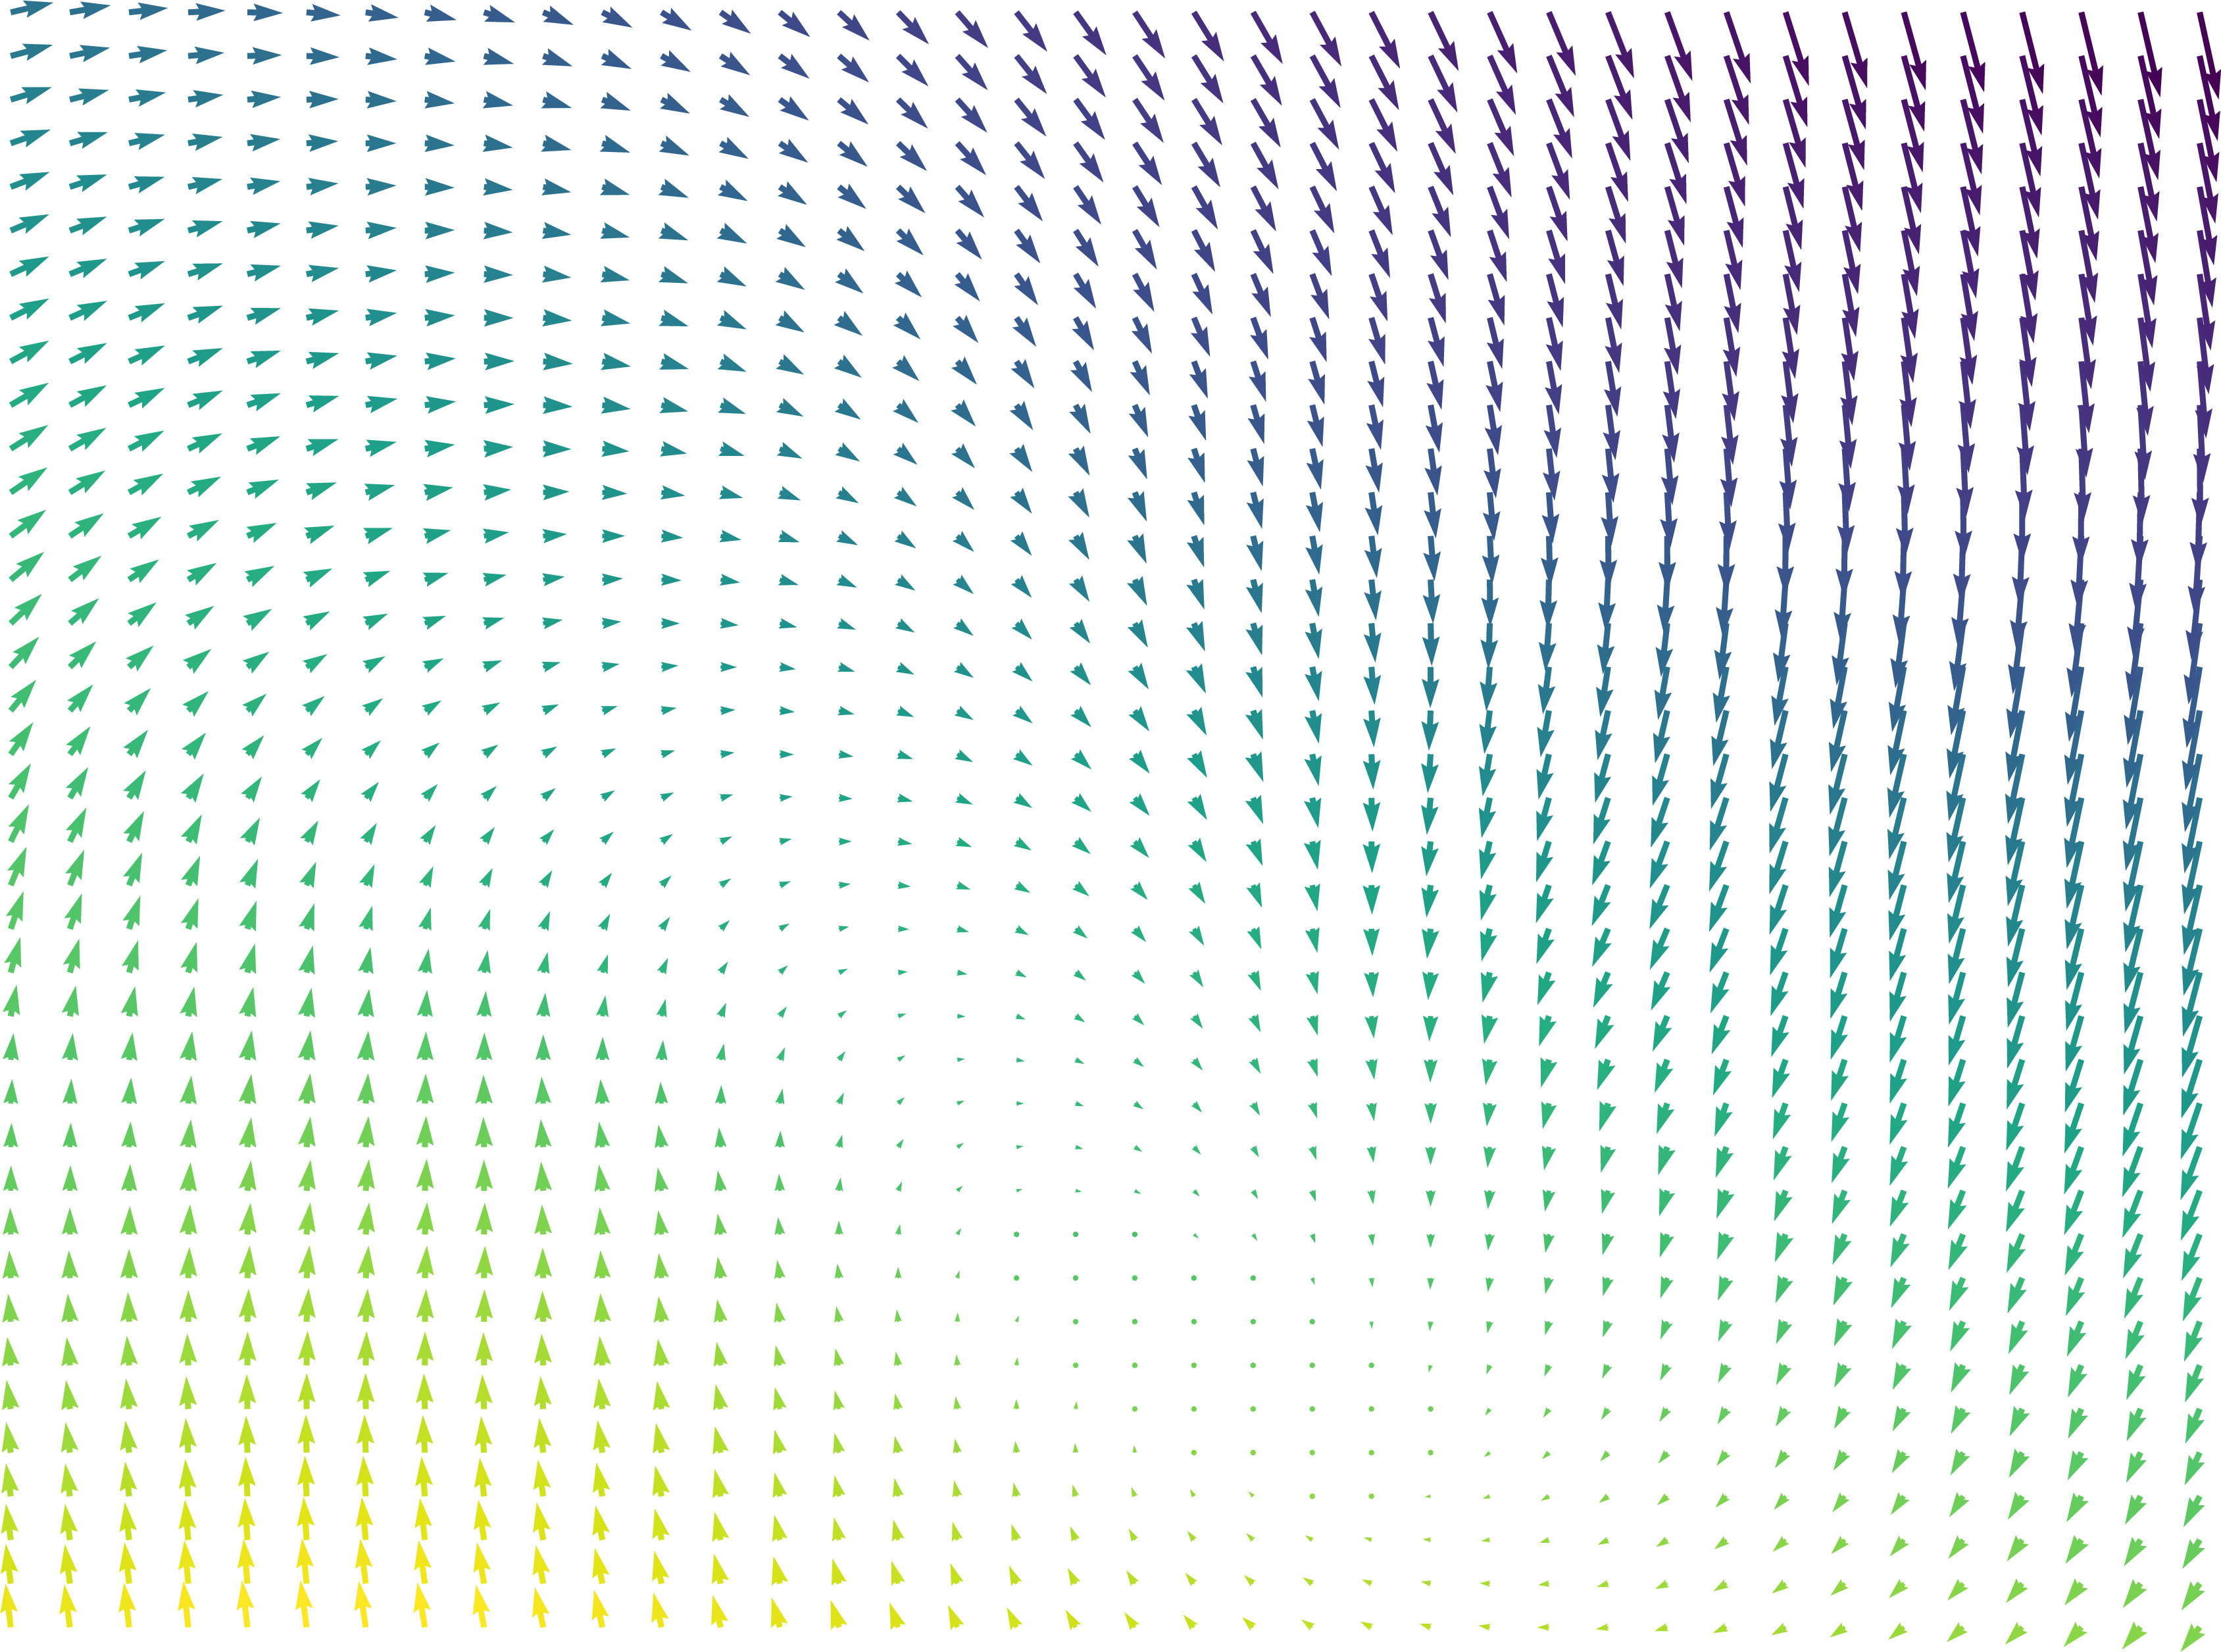

To motivate our work, consider the example in Fig. 1, in which we performed a 3D registration of two MRI brain scans from the OASIS [7] dataset using the popular Stationary Velocity Field (SVF) approach [8, 9, 10] and our proposed method (denoted ). In the first example, the sought deformation is comparably small before the registration process, and both approaches perform equally well. In the second example, the deformation includes a larger rotational component. When looking at the deformed images only, the SVF approach appears to generate an alignment that is clearly worse, but not catastrophically so. This is deceptive: inspecting the generated deformation fields (Fig. 2), it becomes clear that the SVF approach generates a deformation that – while it maps corresponding intensity values reasonably well between the images – is far from the ground truth.

The findings on these (synthetic) examples are compatible with our perception of the existing literature: In general, we found that SVF-based approaches mostly seem to be applied to pre-aligned images, and/or that the judgement of their accuracy is solely based on the similarity of the images after registration or on related proxies, such as the overlap of known segmented regions, that do not necessarily imply sensible deformation fields.

This behavior is clearly visible in Fig. 1 and Fig. 2 shown in the introduction, in which the resultant images as well as an exemplary slice of the deformation field are depicted under small and large deformations. It illustrates how the matrix group approach is able to capture even large rotational deformations, whereas the use of an SVF tends to align the intensity values by local deformations instead of a global rotation, resulting in the large RMSE observed in Fig. 12.